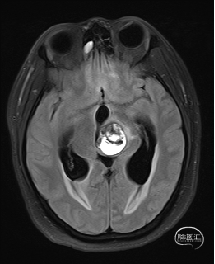

术前MRI检查

术前MRI检查提示左侧丘脑中脑海绵状血管瘤并卒中,梗阻性脑积水;

根据MRI及DTI显示,只有在丘脑与上丘之间的点(dot)进入病变才可能在切除病变时最大程度保护神经功能,由于上述原因,该“点”在术中显露极其困难,虽有导航指引,电生理监测的条件下,对术者的耐心、技术、经验及体能依然是极大的挑战;

本例患者磁共振检查清晰显示病变位于左侧丘脑中脑区域,且位于丘脑内下方向中脑顶盖延续,病变的上部、前部、外侧部都有重要的神经组织,因此,手术从上方、前方、外侧方向切除病变均难以实施;

术前详细的磁共振检查,包括平扫增强,SWI及DTI,可以规划出手术最适宜的路径及切入点;